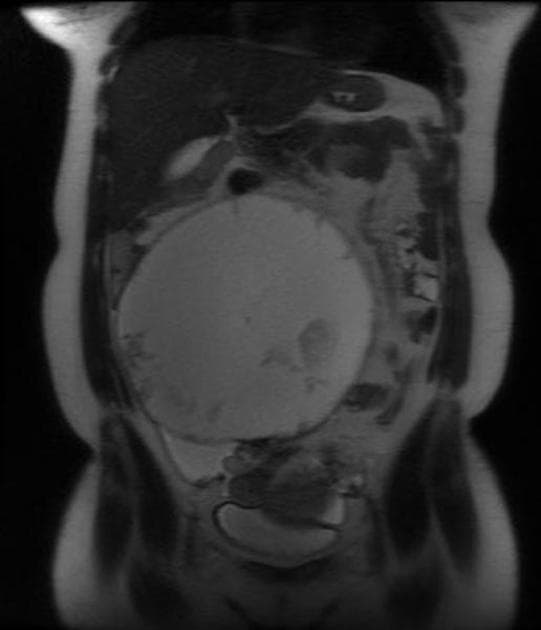

- Nang đa thùy bên trái buồng trứng trái (left ovarian multi-locular cyst) với các thành phần dạng nang và xuất huyết (cystic and hemorrhagic components), trên cộng hưởng từ:

- Tín hiệu tăng trên hình ảnh trọng T1 (high signal at T1 WI),

- Tín hiệu giảm trên hình ảnh trọng T2 (low signal at T2 WI),

- Tín hiệu tăng trên chuỗi ức chế mỡ (high signal at fat sat sequences), loại trừ bản chất chứa mỡ và gợi ý thành phần xuất huyết (suggests hemorrhagic components).

- Nang có tăng quang nhẹ ở viền sau tiêm thuốc đối quang (mild marginal post contrast enhancement).

Hình ảnh cộng hưởng từ (MR) cho thấy nhiều u lạc nội mạc tử cung (multiple endometriomas).

- "U lạc nội mạc tử cung thường biểu hiện là nang buồng trứng tăng tín hiệu trên T1, giảm tín hiệu trên T2 do xuất huyết mạn tính."

- "Chuỗi ức chế mỡ giúp phân biệt u lạc nội mạc tử cung với nang da bằng cách loại trừ mỡ vĩ mô."

- "Tăng quang viền là đặc điểm phổ biến ở u lạc nội mạc tử cung, phản ánh lớp vỏ xơ hoặc viêm hoạt động."

Lạc nội mạc tử cung là tình trạng mô giống nội mạc tử cung xuất hiện bên ngoài buồng tử cung, thường ảnh hưởng đến buồng trứng và tạo thành các u lạc nội mạc tử cung. Những 'nang sô cô la' này đặc trưng bởi tình trạng xuất huyết tái diễn, dẫn đến tăng tín hiệu trên T1 và 'che phủ' trên T2 (giảm tín hiệu trên T2 do hàm lượng protein cao hoặc lắng đọng hemosiderin). Cộng hưởng từ (MRI) có độ nhạy cao trong việc phát hiện các tổn thương này, chuỗi ức chế mỡ xác nhận sự vắng mặt của mỡ, từ đó phân biệt với nang da. Sự hiện diện của nhiều u lạc nội mạc tử cung làm tăng khả năng chẩn đoán. Việc mô tả hình ảnh chính xác rất quan trọng cho lập kế hoạch phẫu thuật và bảo tồn khả năng sinh sản.